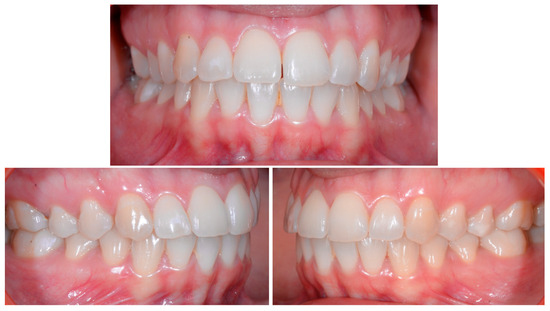

A 22-year-old female patient in good health had a consultation because she was concerned about the “root prominence” of tooth 41. She wore a mandibular retainer wire when she was 16 years old at the end of her orthodontic treatment. She has good oral hygiene, despite the presence of tartar between 31 and 41, and a right and left Class I with a slight deviation of the midlines (Figure 1).

Figure 1.

Early wire syndrome. Frontal and lateral views.

In Figure 2, the following can be observed: a difference in gingival margin height between 41 and 31, a difference in height of the incisal edges of 41 compared to the adjacent teeth, and the onset of gingival recession on 41 associated with the visibility of a vestibular arch corresponding to its root.

Figure 2.

Early wire syndrome. Frontal views.

In the lateral view (Figure 3), the prominence of the root of 41 was confirmed.

Figure 3.

Early wire syndrome. Lateral view.

Occlusal views (Figure 4) confirmed the presence of a mandibular retainer which appears intact, without fracture or debonding, along its entire length. In addition, the vestibular surface of 41 appeared to have a difference in visibility from the adjacent teeth. Based on these clinical findings, wire syndrome starting on tooth 41, called the “X-effect” type, was suspected.

Figure 4.

Early wire syndrome. Occlusal view.